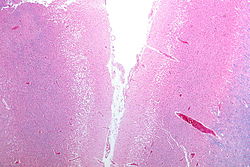

Ishemijski moždani udar nastaje zbog gubitka opskrbe krvlju dijela mozga što pokreće ishemijsku kaskadu[29]. Moždano tkivo prestaje funkcionirati ako je uskraćen dotok kisika dulje od 60 do 90 sekundi, a nakon otprilike tri sata dolazi do nepovratnih ozljeda koje dovode do smrti tkiva, tj. do moždanog udara. (To je razlog zašto se fibrinolitici, kao što je alteplaza, daju samo unutar tri sata od nastanka moždanog udara.) Ateroskleroza može poremetiti dotok krvi suženjem lumena krvne žile što dovodi do smanjenja protoka krvi i posljedično do stvaranja krvnih ugrušaka u krvnoj žili ili otpuštanjem mnoštva komadića malih embolusa raspadom ateroskelortskih plakova[30]. Embolijski infarkti nastaju kada se embolusi formirani negdje drugdje u tijelu, obično u srcu kao posljedica atrijske fibrilacije ili u karotidnim arterijama, otkinu, uđu u moždanu cirkulaciju, te se smjeste i začepe krvnu žilu. Budući da su sad krvne žile u mozgu začepljene, u mozgu pada razina energije, što rezultira prijelazom na anaerobni metabolizam u području moždanog tkiva zahvaćenog ishemijom. Nažalost, ova vrsta metabolizma proizvodi manje adenozin trifosfata (ATP), ali ispušta i nusproizvod pod nazivnom mliječna kiselina. Mliječna kiselina je iritans koji mi mogao uništiti stanice, jer je kiselina i ometa normalnu acido-baznu ravnotežu u mozgu. Područje ishemije se naziva „ishemijska penumbra“[31].

Zatim, dolazi do smanjenja koncentracije kisika i glukoze u području ishemije, proizvodnja viskoenergetskih fosfatnih spojeva kao što je adenozin trifosfat (ATP) ne uspijeva, što dovodi do propadanja energetski ovisnih procesa (kao što je rad ionskih pumpi) potrebnih za preživljavanje stanice. To dovodi do pokretanja cijelog niza povezanih događaja što kao posljedicu ima oštećenje stanice i njezinu smrt. Glavni uzrok ozljede neurona je oslobađanje stimulacijskog neurotransmitera glutamata. Koncentracija glutamata izvan stanica živčanog sustava obično se održava niskom uz pomoć tzv. apsorpcije nosača, koji se napaja iz koncentracijskog gradijenta iona (uglavnom Na+) preko stanične membrane. Međutim, moždani udar prekida dotok kisika i glukoze koji pokreću te ionske pumpe potrebne za održavanje tih gradijenata. Kako rezultat nastaje pad ionskog gradijenta i glutamatni tranporteri preokreću svoj smjer, otpuštajući glutamat u izvanstanični prostor. Glutamat djeluje na receptore na živčanim stanicama (posebice NMDA receptore), dovodeći do priljeva kalcija koji aktivira enzime koji razgrađuju stanične bjelančevine, lipide i sadržaj jezgre. Priljev kalcija također može dovesti do propasti mitohondrija, što može dalje dovesti do gubitka energije i može potaknuti staničnu smrt putem apoptoze.

Ishemija također potiče nastanak slobodnih radikala kisika i drugih reaktivnih kisikovih spojeva. Oni reagiraju s brojnim staničnim i izvanstaničnim strukturama i oštećuju ih. Posebno je važno oštećenje sluznice ili endotela krvnih žila. U stvari, mnogi neuroprotektivni antioksidansi poput mokraćne kiseline i NXY-059 djeluju na nivou endotela, a ne na moždanom tkivu. Slobodni radikali također mogu izravno pokrenuti elemente kaskade apoptoze pomoću redoks signalizacije.

Ti procesi su isti za bilo koju vrstu ishemijskog tkiva i nazivaju se zajedničkim imenom ishemijskom kaskadom. Međutim, moždano tkivo je posebno ranjivo na ishemiju jer ima malu respiratornu rezervu i potpuno je ovisno o aerobnom metabolizmu, za razliku od većine drugih organa.

Osim štetnih utjecaja na moždane stanice, ishemija i infarkt mogu rezultirati gubitkom i strukturalnog integriteta moždanog tkiva i krvnih žila, dijelom kroz oslobađanje metaloproteinaza, koje su cink i kalcij ovisni enzimi koji razgrađuju kolagen, hijaluronsku kiselinu i druge elemente vezivnog tkiva. Ostale proteaze također pridonose ovom procesu. Gubitak integriteta vaskularnih struktura rezultira slomom zaštitne krvno-moždane barijere i doprinosi moždanom edemu, koji može uzrokovati sekundarnu progresiju moždane ozljede.

Hemoragijski moždani udar

Hemoragijski moždani udar rezultira ozljedom tkiva uslijed kompresije tkiva prilikom širenja jednog ili više hematoma. To može narušiti i ozlijediti tkivo. Osim toga, tlak može dovesti do gubitka krvne opskrbe u zahvaćenom području što rezultira infarktom, a krvi otpuštena prilikom moždanog krvarenja čini se da ima izravno toksično djelovanje na moždano tkivo i krvne žile. Upala doprinosi sekundarnom oštećenju nakon krvarenja[15][32] Inflammation contributes to the secondary brain injury after hemorrhage.[32] .